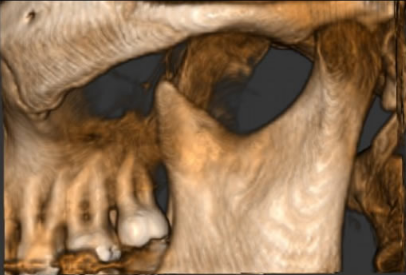

Proactive Dental Management thru our 3D Imaging Manipulation Software

With Oral Maxillofacial CT Scans, your dentist enhances his ability to proactively manage your health concern thru accurate diagnosis & better treatment planning. Moreover, the patient benefits from a painless,low radiation dose CT Scan procedure.